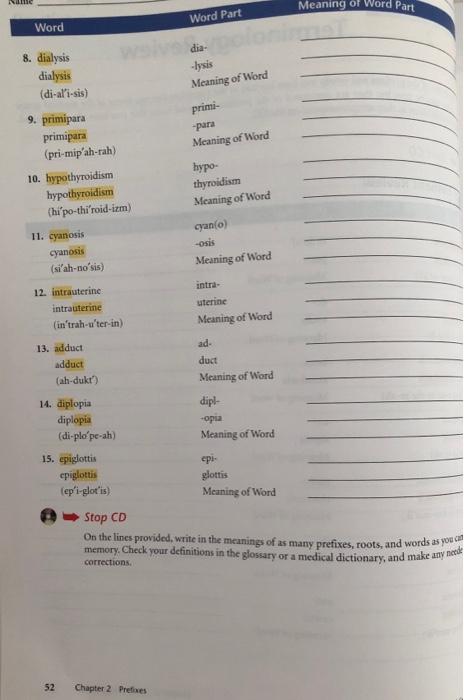

Solved Ne Meaning of Word Part Word Part Word 8. dialysis | Chegg.com